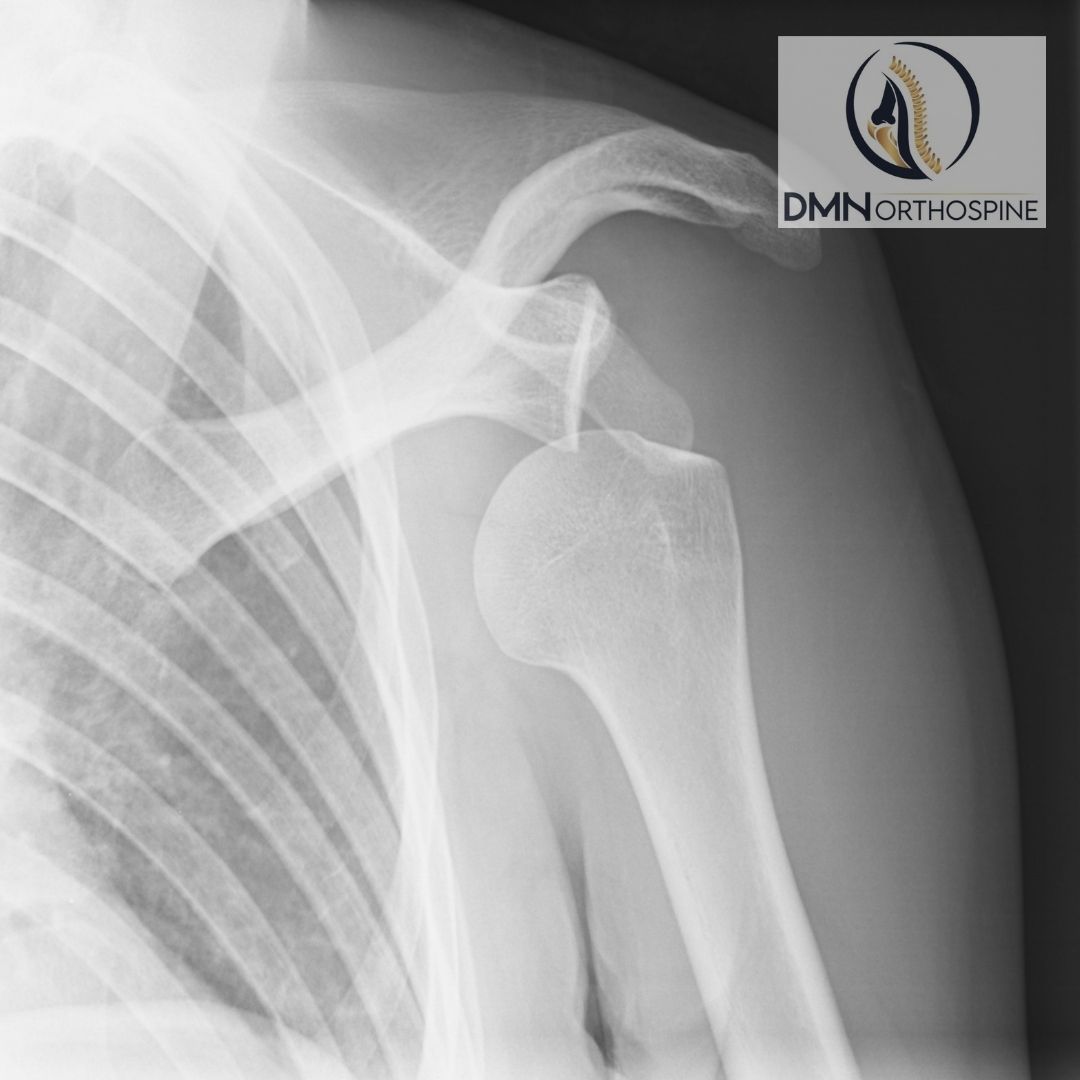

تسمى المجموعات العضلية التي توفر حركة مفصل الكتف بالكفة المدورة (الكفة). عند الشباب ، قد تحدث تمزق في هذه المجموعة العضلية في حركات مثل السقوط وتعليق الذراع ورفع الأثقال غير المنضبط. في الأعمار المتقدمة ، يحدث تمزق جزئي ثم كامل السماكة بسبب تآكل وترقق الشعاع العضلي. عادة ما تكون السلالات المتكررة ، وعدم كفاية إمدادات الدم وضغط العظام في الكتف بسبب طاولة التآكل هذه التي تظهر في الأعمار الأكبر.

لوحظ تقصير وفقدان السمة (التنكس الدهني) في العضلات الممزقة ذات السماكة الكاملة بمرور الوقت. مع شد العضلة ، تبدأ عظام الكتف في الاحتكاك وتصبح صورة تكلس الكتف واضحة بمرور الوقت.